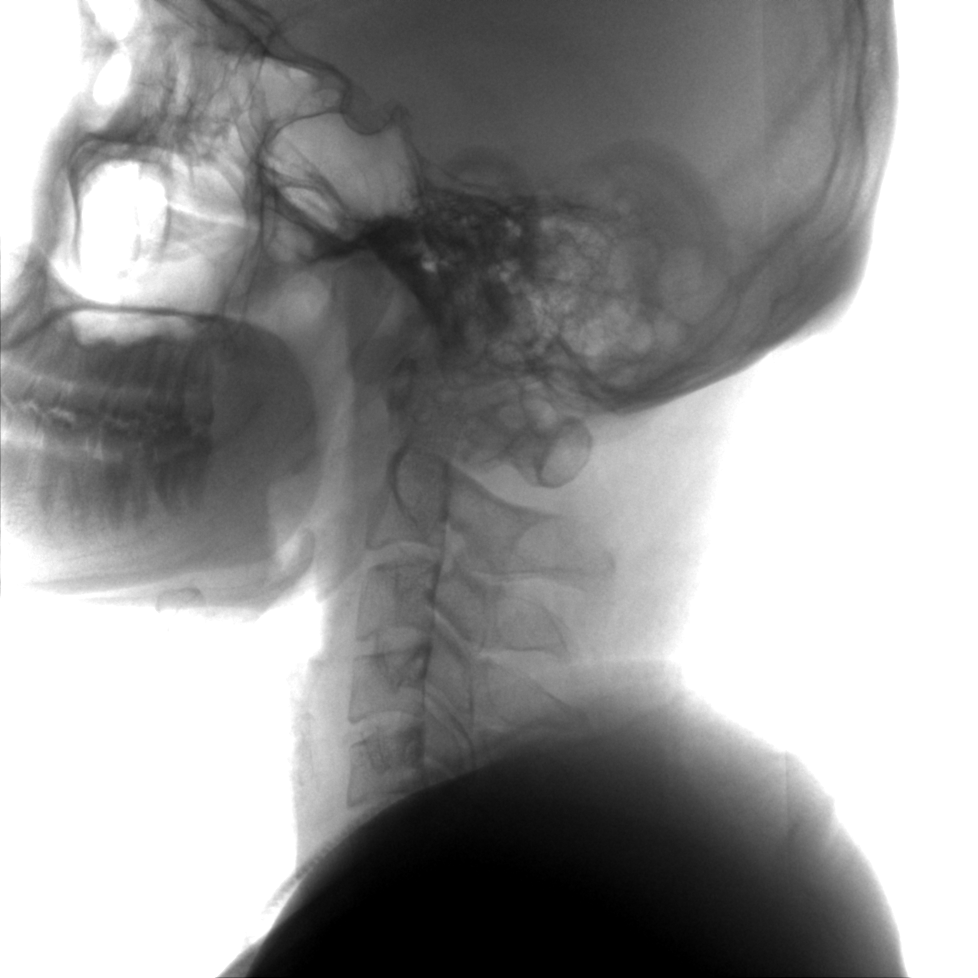

提供更大的術中三維成像視野,采集更多圖像信息,可一次拍全全段頸椎、全段腰椎、七節胸椎、雙側骶髂關節、股骨頭及單側盆骨。

術中三維成像和橫斷面圖像提供多角度的手術診斷信息,輔助醫生進行術中評估判斷,諸如骨折復位情況和內植入螺釘的尺寸和位置,輔助手術更好地完成。